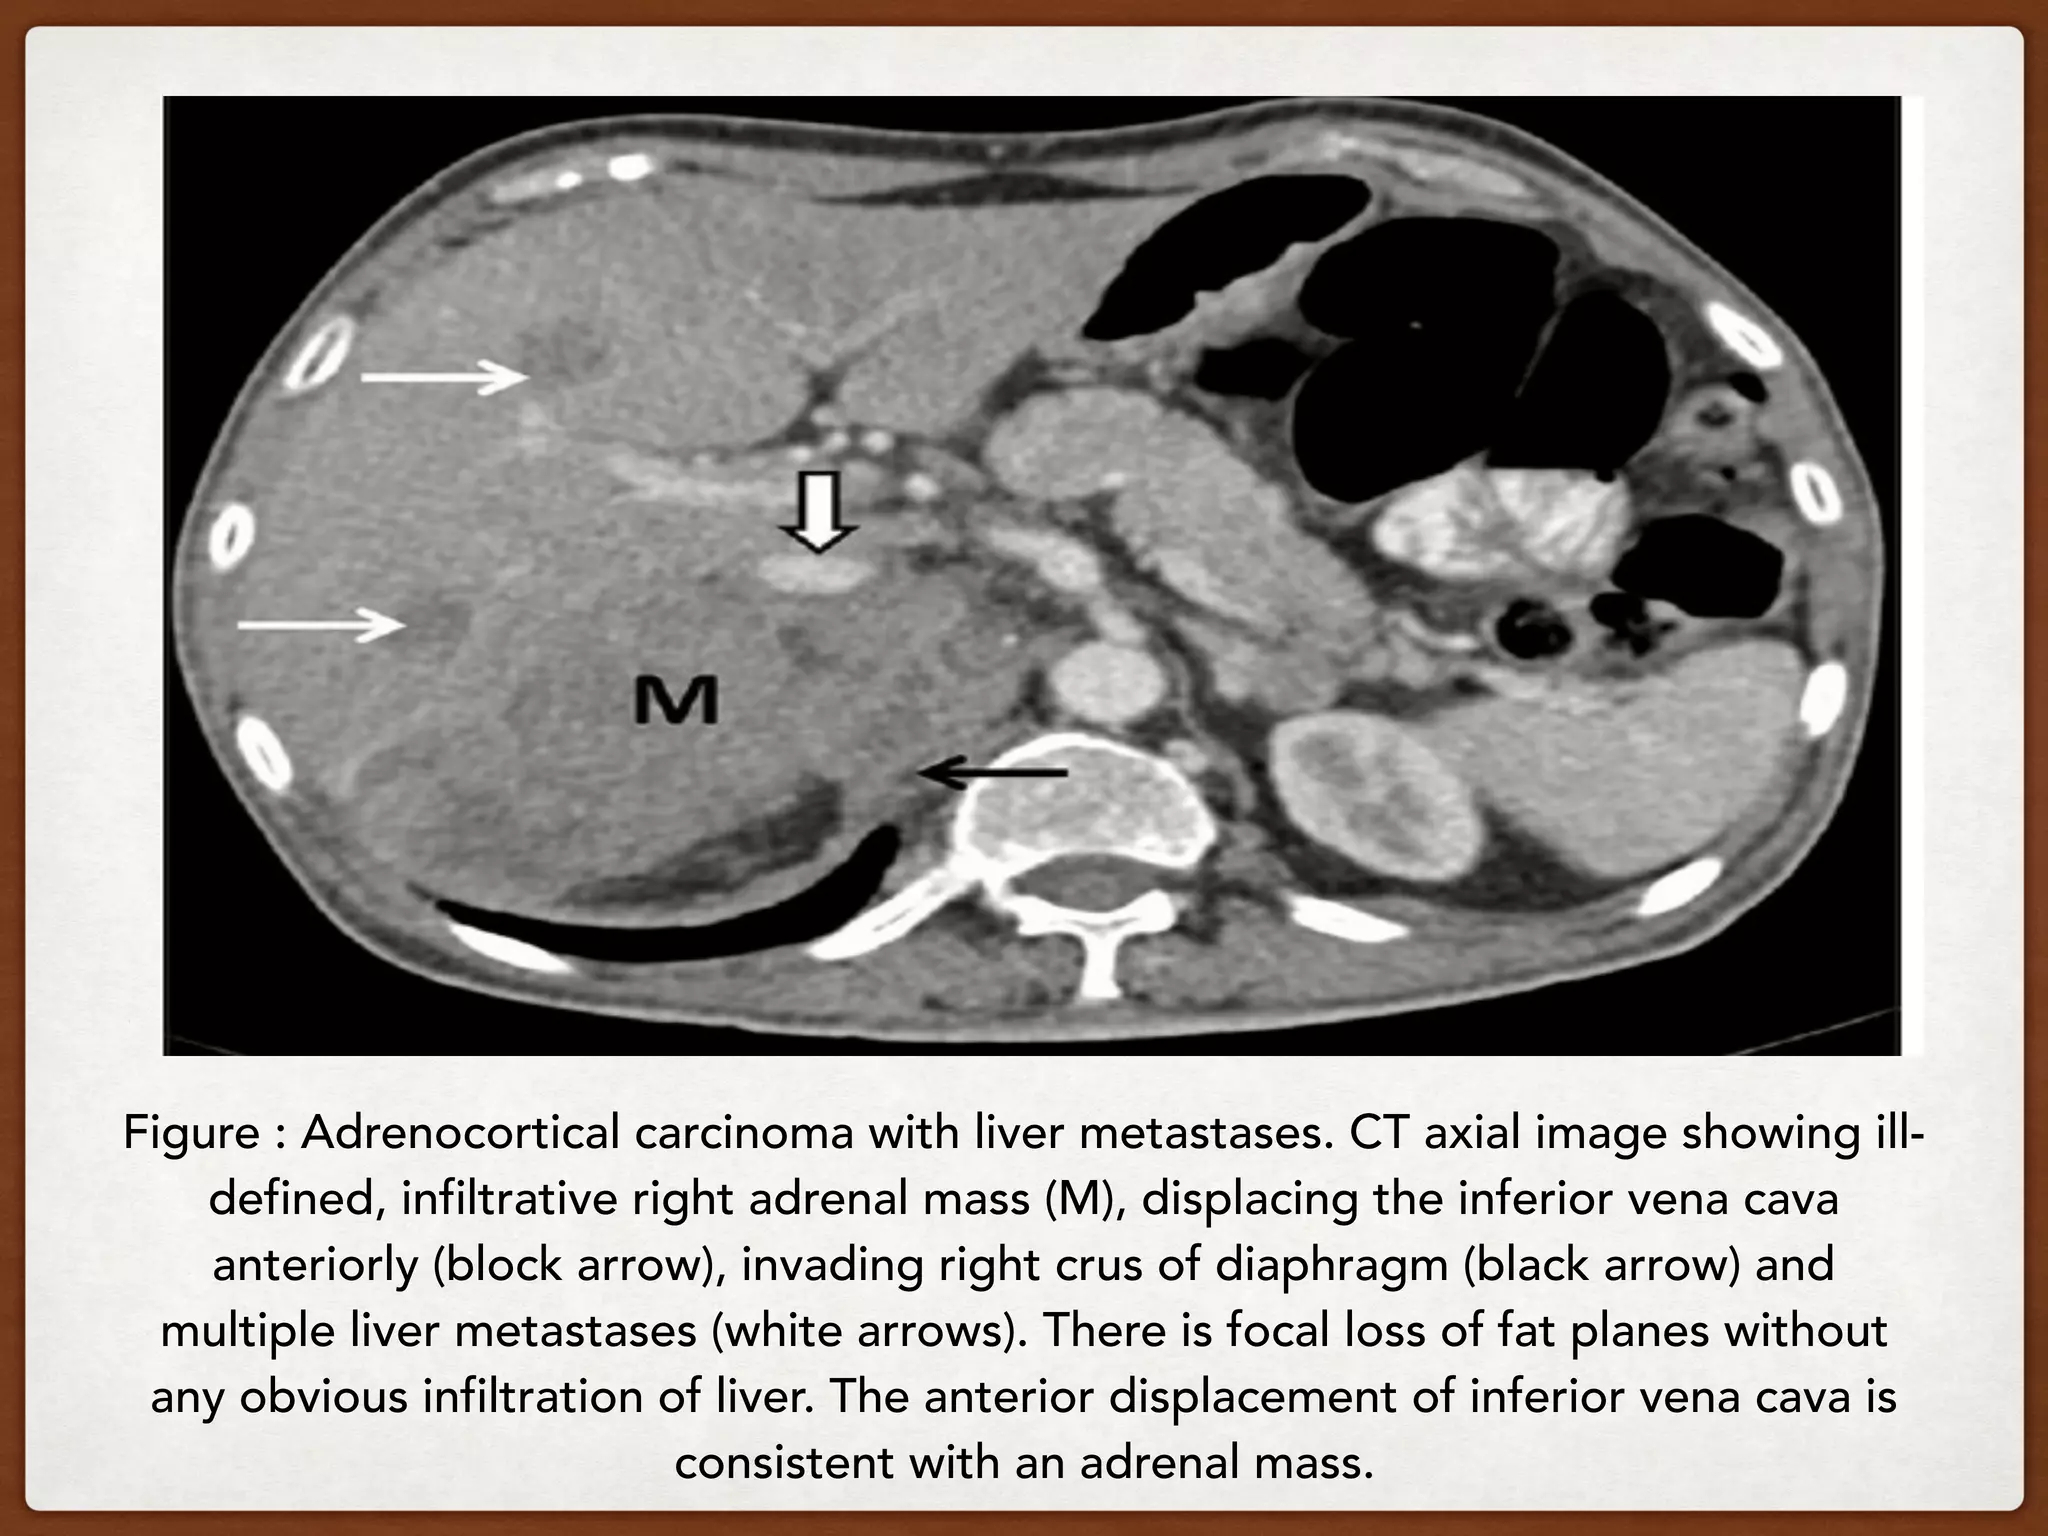

Figure : Adrenocortical carcinoma with liver metastases. CT axial image showing ill-

defined, infiltrative right adrenal mass (M), displacing the inferior vena cava

anteriorly (block arrow), invading right crus of diaphragm (black arrow) and

multiple liver metastases (white arrows). There is focal loss of fat planes without

any obvious infiltration of liver. The anterior displacement of inferior vena cava is

consistent with an adrenal mass.

Figure : Adrenocorticalcarcinoma with liver metastases. CT axial image showing ill- defined, infiltrative right adrenal mass (M), displacing the inferior vena cava anteriorly (block arrow), invading right crus of diaphragm (black arrow) and multiple liver metastases (white arrows). There is focal loss of fat planes without any obvious infiltration of liver. The anterior displacement of inferior vena cava is consistent with an adrenal mass.